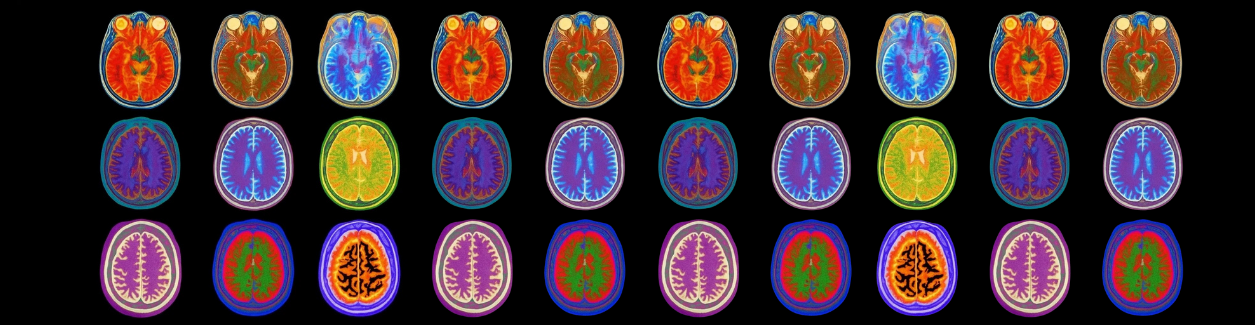

Všichni psali stejnou esej. Jen za jiných podmínek. Jedna skupina psala s ChatGPT, druhá mohla googlit a třetí tvořila text úplně bez pomoci. Během psaní měli na hlavě EEG senzory, které měřily mozkovou aktivitu a konektivitu. Tedy to, jak mezi sebou jednotlivé oblasti mozku komunikují. Pak se skupiny prohodily. Ti, kdo psali s AI, psali bez ní, a naopak. Autoři dodávají, že cílem bylo pochopit, jak různé způsoby tvorby ovlivňují mentální zátěž, pozornost a vlastnictví textu.

Výzkum naznačuje, že skupina, která psala s ChatGPT, vykazovala nižší mozkovou konektivitu a slabší aktivitu než ti, kteří psali sami. Skupina s Googlem dopadla mezi nimi.

Když se účastníci, kteří původně psali s AI, začali psát bez ní, jejich mozková aktivita zůstala utlumenější. Autoři popisují, že působila, jako by mozek zůstal „na autopilotu“. Zároveň účastníci hůř citovali své vlastní texty a měli slabší pocit, že „tohle je můj text“.